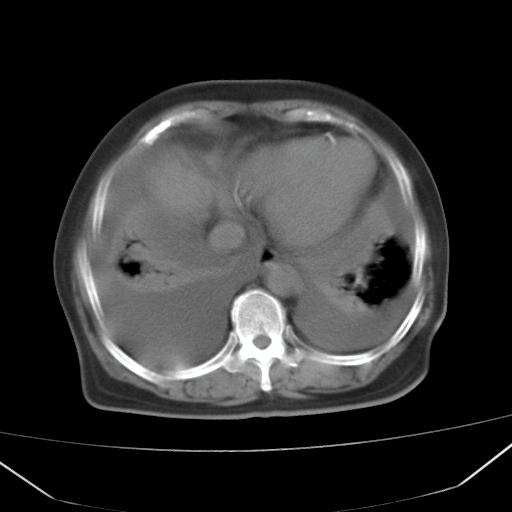

以下是引用liuyue在2008-4-19 22:25:00的发言:[br]先考虑:1.心衰伴肺水肿、双侧胸腔积液、叶间积液、双下肺不完全性肺不张; [br] 2.冠状动脉粥样硬化。

以下是引用lijuanln在2008-4-19 23:05:00的发言:[br]两侧胸腔积液,肺水肿[br]心包积液[br]提示心衰

以下是引用jiangjing在2008-4-20 10:43:00的发言:[br]结合病史支持 冠心病[冠状动脉钙化],心功能不全,肺淤血、肺水肿,双侧胸腔与斜裂积液